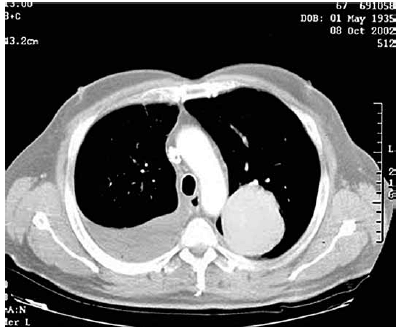

Paciente do sexo masculino, 45 anos, procura ambulatório de clínica médica relatando que há dois meses iniciou quadro de dor em hemitórax direito que piorava com a inspiração profunda. Essa dor diminuiu gradualmente ao mesmo tempo que surgiram episódios de febre baixa (37,9 oC) sempre no final da tarde. Relata emagrecimento de 9 kg nesse período. Tabagista 40 anos/maço. Nega antecedentes mórbidos pessoais ou contato com pessoas doentes. Após exame físico, o médico solicita uma tomografia computadorizada de tórax que está apresentada a seguir.

A dosagem da adenosina desaminase

A principal hipótese diagnóstica é: